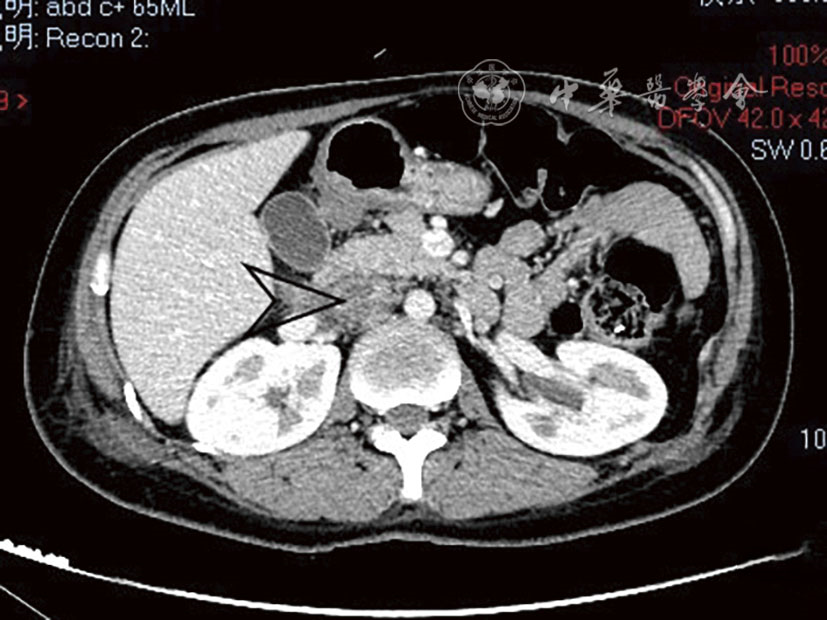

Tao Chen, Hongjian Shi, Liang Zhou, Zhen Gan.

Interventional treatment for delayed postoperative hemorrhage after gastric and pancreatic-biliary surgery

[J]. Chinese Journal of Interventional Radiology(Electronic Edition), 2024, 12(01): 39-44.